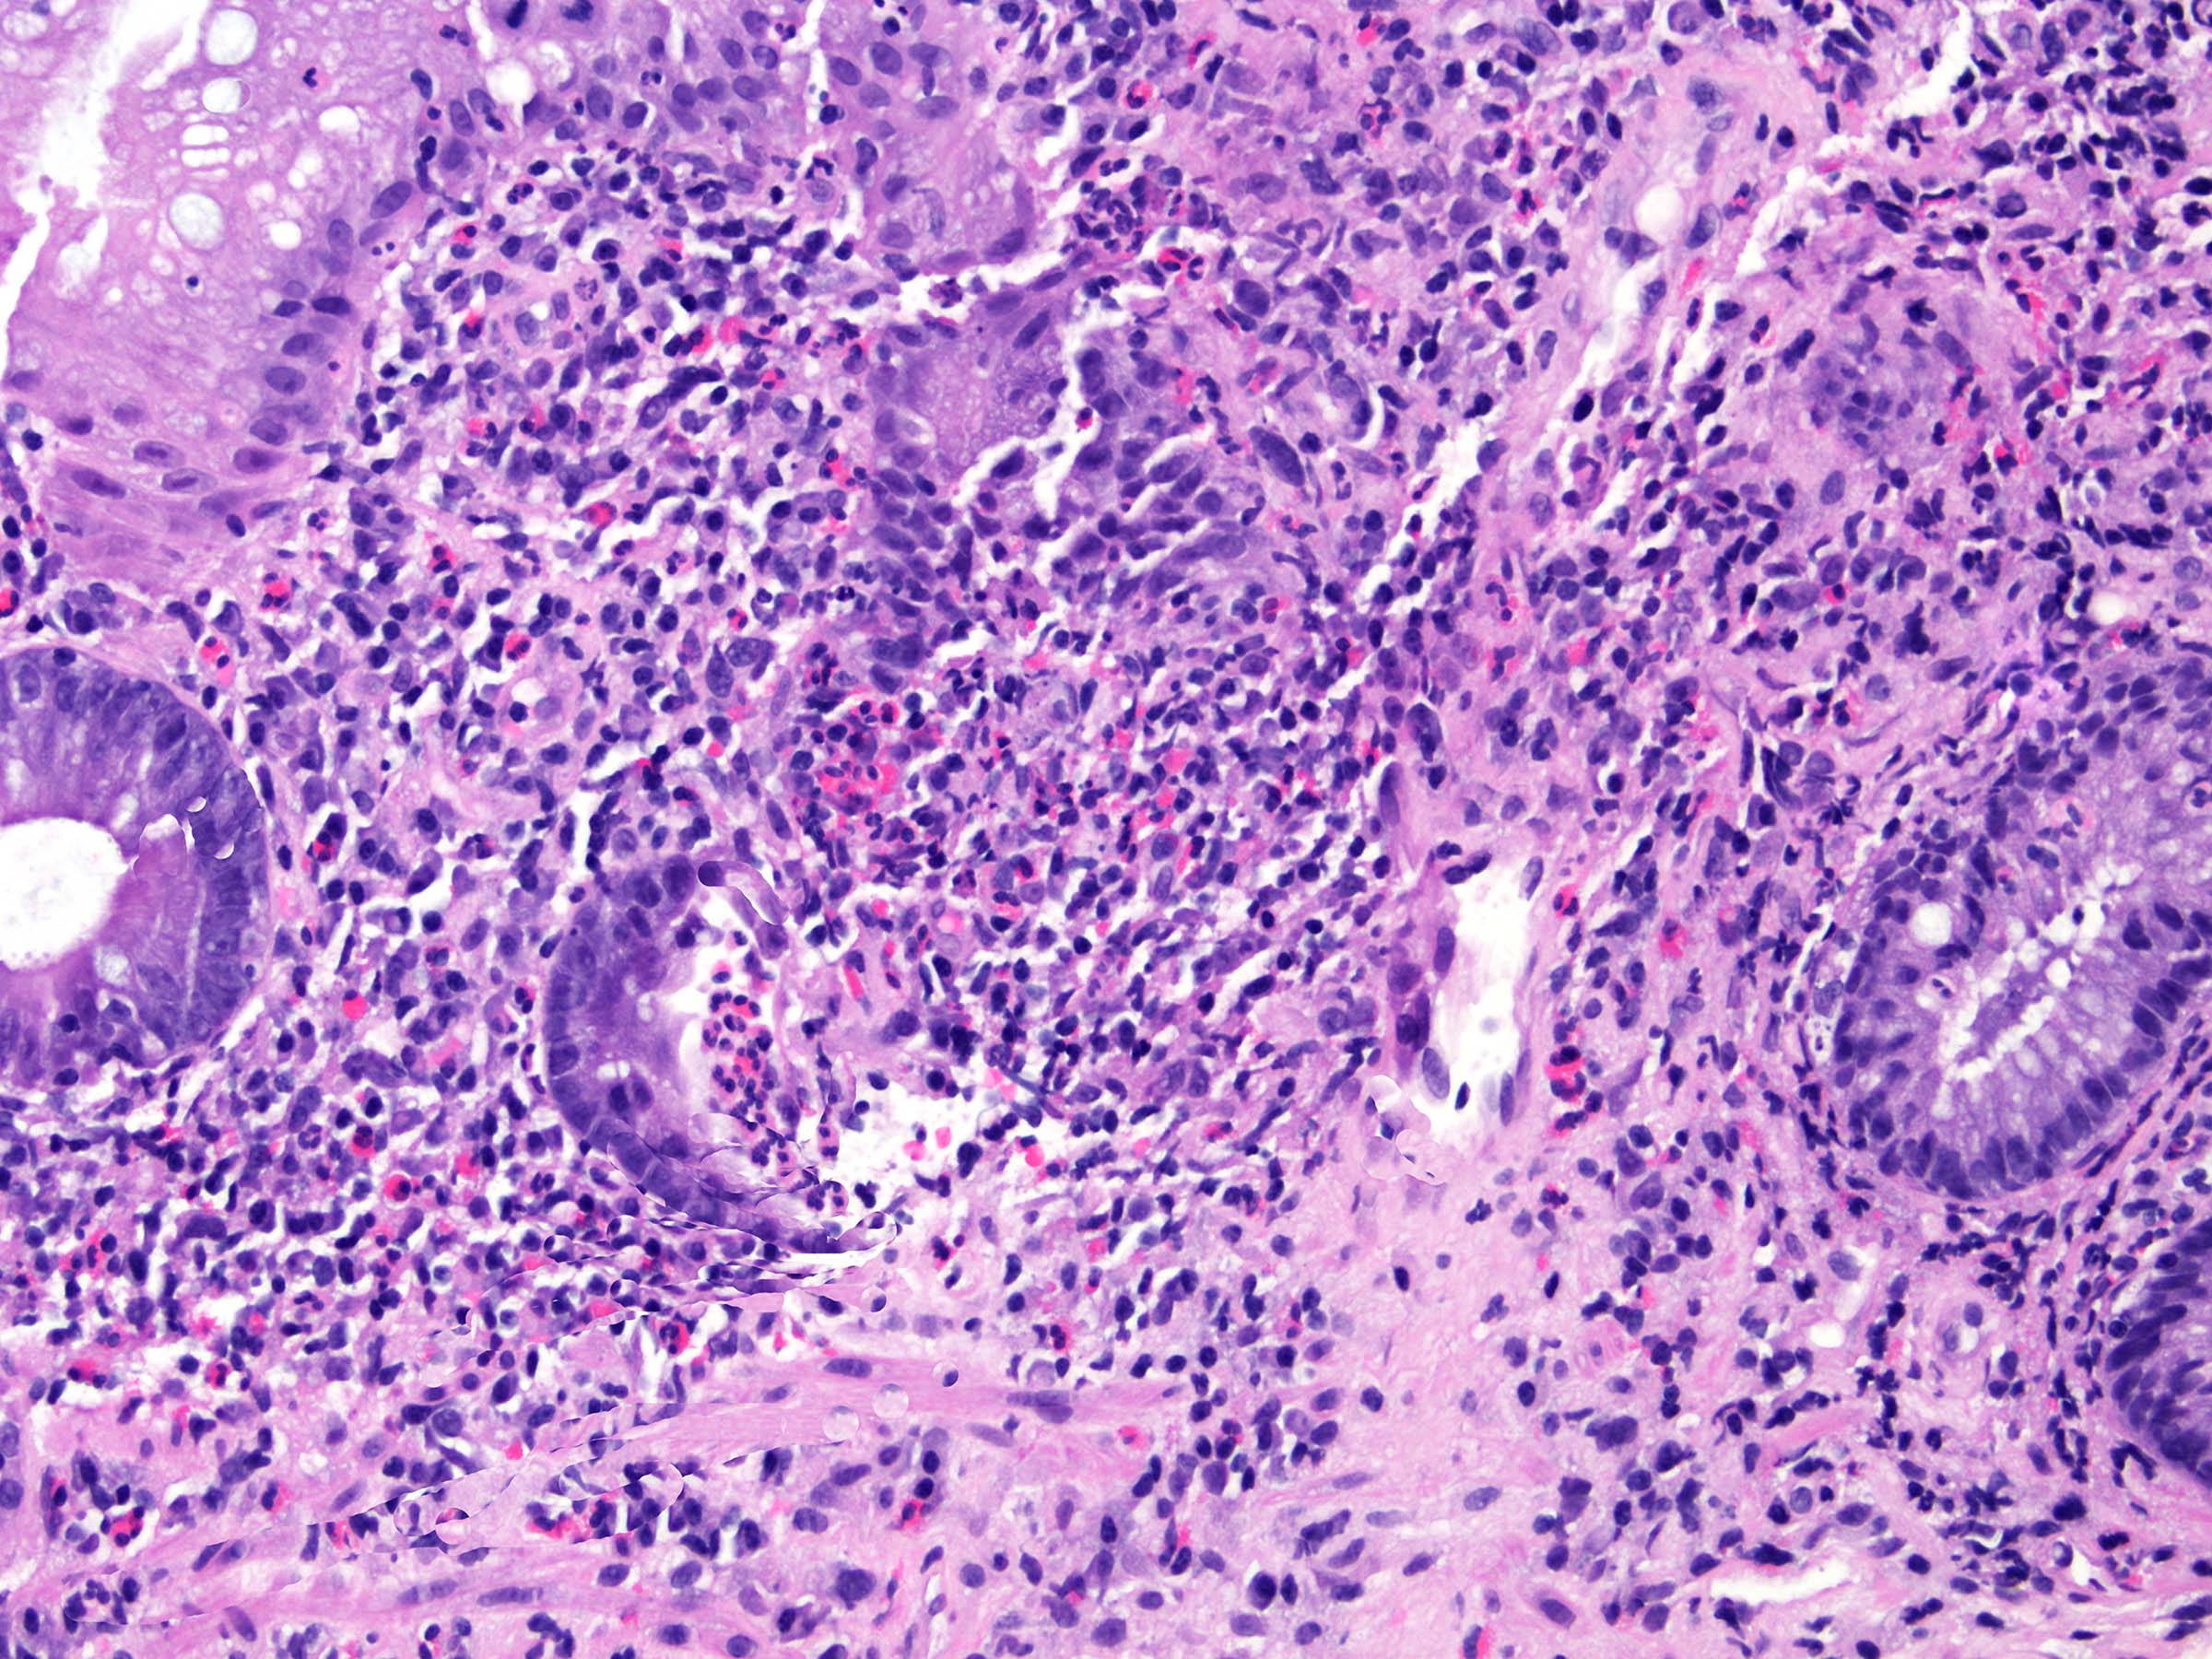

Microscopic (histologic) images

Microscopic (histologic) description

- Acute radiation colitis (< 6 months after radiation treatment):

- Inflammation

- Typically eosinophilic (characteristic)

- Lamina propria eosinophilic infiltration

- Eosinophilic cryptitis

- Eosinophilic crypt abscesses

- Typically eosinophilic (characteristic)

- Can be fibroblast proliferation in lamina propria (reactive changes to radiation)

E. Radiation colitis, chronic. Chronic radiation colitis is expected at > 6 months postradiation therapy. Sections show ulcerations, mild epithelial atypia, architectural changes and atrophy. The lamina propria contains fibrosis, mild chronic inflammation and fibroblast atypia (enlarged hyperchromatic nuclei). The vasculature within submucosal and deeper layers contains hyalinization of vessel wall and intimal thickening. Vascular ectasia, narrowing and thrombosis can also be present. Collagenous colitis (answer A) typically presents with history of watery diarrhea and a > 10 μM subepithelial collagen table (collagenous band). Infection (bacterial) (answer B) will present with an acute clinical history (example: diarrhea and vomiting) after an inciting event (example: food consumption, travel). Acute colitis and granulomas can sometimes be seen. Viral infections (example: cytomegalovirus, Epstein-Barr virus) can occur in immunocompromised patients (example: HIV or transplant) and will contain atypical cells with nuclear changes. Mucosal prolapse (answer C) can present endoscopically as a polyp and contains ingrowth of thick muscle bundles that can mechanically squeeze ensnared epithelium. This is accompanied by variable inflammation, ulceration and reaction epithelial change. Acute radiation colitis (answer D) is expected at < 6 months postradiation therapy. The inflammation is typically eosinophilic (characteristic) with eosinophilic cryptitis, crypt abscesses and lamina propria eosinophilia. Sections demonstrate reduced mitotic activity, apoptosis, reduced goblet cell mucin, goblet cell swelling, degenerative changes and atypia (nuclear enlargement and malorientation).